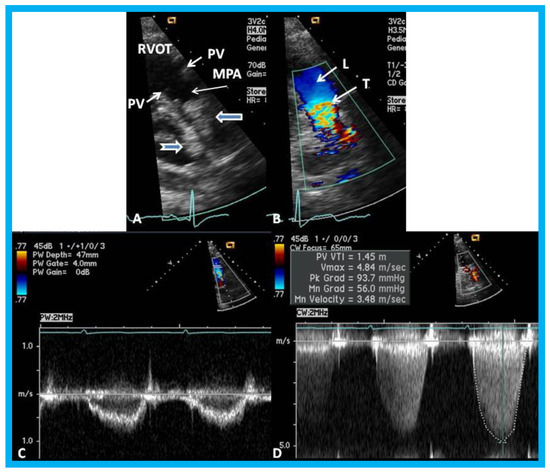

Figure 21. (A) Selected video frame from a parasternal short axis view showing echo dense structures (thick blue arrows) within and outside the main pulmonary artery (MPA): Pulmonary valve (PV) leaflets (small arrows) are shown and appear normal. The right ventricular outflow tract (RVOT) and proximal MPA are free of any echo-dense structures. (B) Color-Doppler mapping of the same structures as in panel A shows normal laminar (L) flow in the RVOT and proximal MPA and turbulent (T) flow starting in the proximal MPA, indicating obstruction. (C) Pulse Doppler sampling from the proximal MPA, which shows normal flow velocity. (D) Continuous wave Doppler sampling demonstrating high velocity flow across the MPA with a calculated peak instantaneous gradient of 93.7 mmHg and a mean gradient of 56 mmHg, indicating severe obstruction. Reproduced from Mazur L., et al. [31].